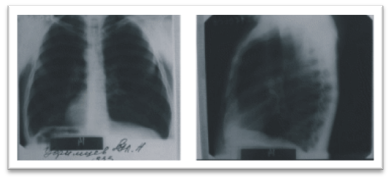

3-ші сурет (б). Екі бағытта түсірілген флюорограммалар (100х100 мм)